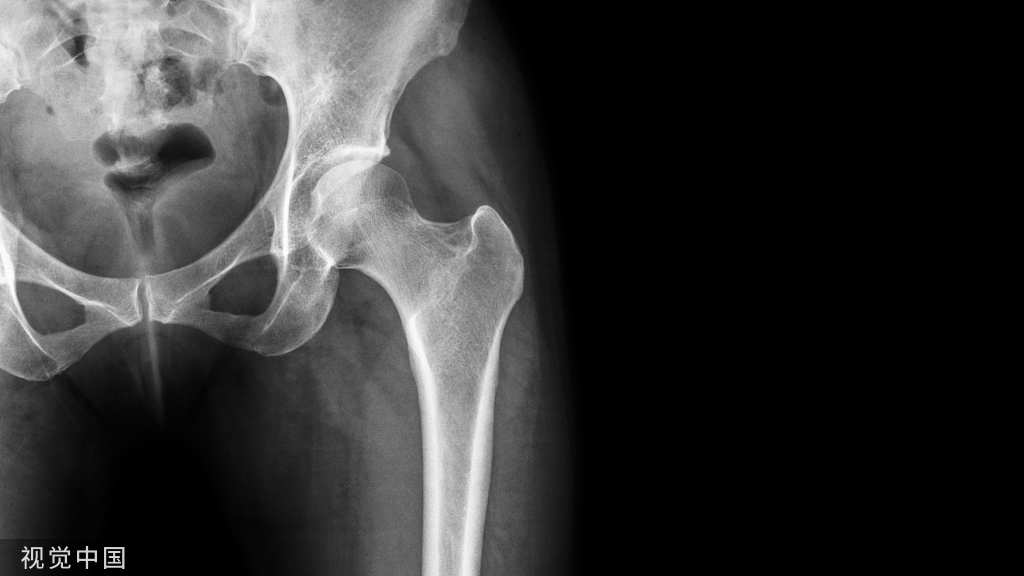

腰臀部皮神经卡压综合征

臀上皮神经卡压症

临床表现与诊断(一) 大多数病人有腰部扭伤史或受风寒史。(二) 主要表现为患侧腰臀部尤其是臀部的疼痛,呈刺痛、酸痛或撕裂样疼痛。而且疼痛常常是持续发生的,很少有间断发生。一般疼痛的部位较深,区域模糊,没有明确的界限。急性期疼痛较剧烈,并可向大腿后侧放散,但常不超过膝关节。患侧臀部可有麻木感,但无下肢麻木。(三) 患者常述起坐困难,弯腰时疼痛加重。(四) 多数病人可以检查到固定的压痛点,一般在髂嵴中点及其下方压痛,按压时可有胀痛或麻木感,并向同侧大腿后方放射,一般放射痛不超过膝关节。直腿抬高试验多为阴性,但有10%的患者可出现直腿抬高试验阳性。腱反射正常。